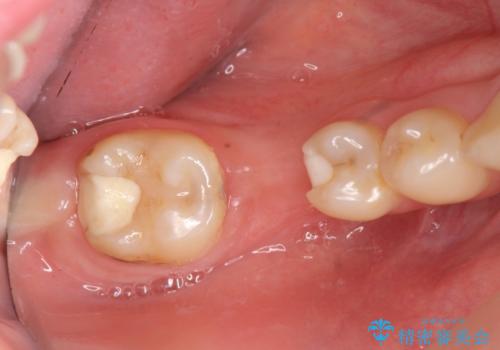

臼歯インプラント補綴

- 虫歯で歯を失い、インプラント治療を希望され来院されました。

吸収した骨を造骨にて補い、インプラントによる機能回復を計画します。